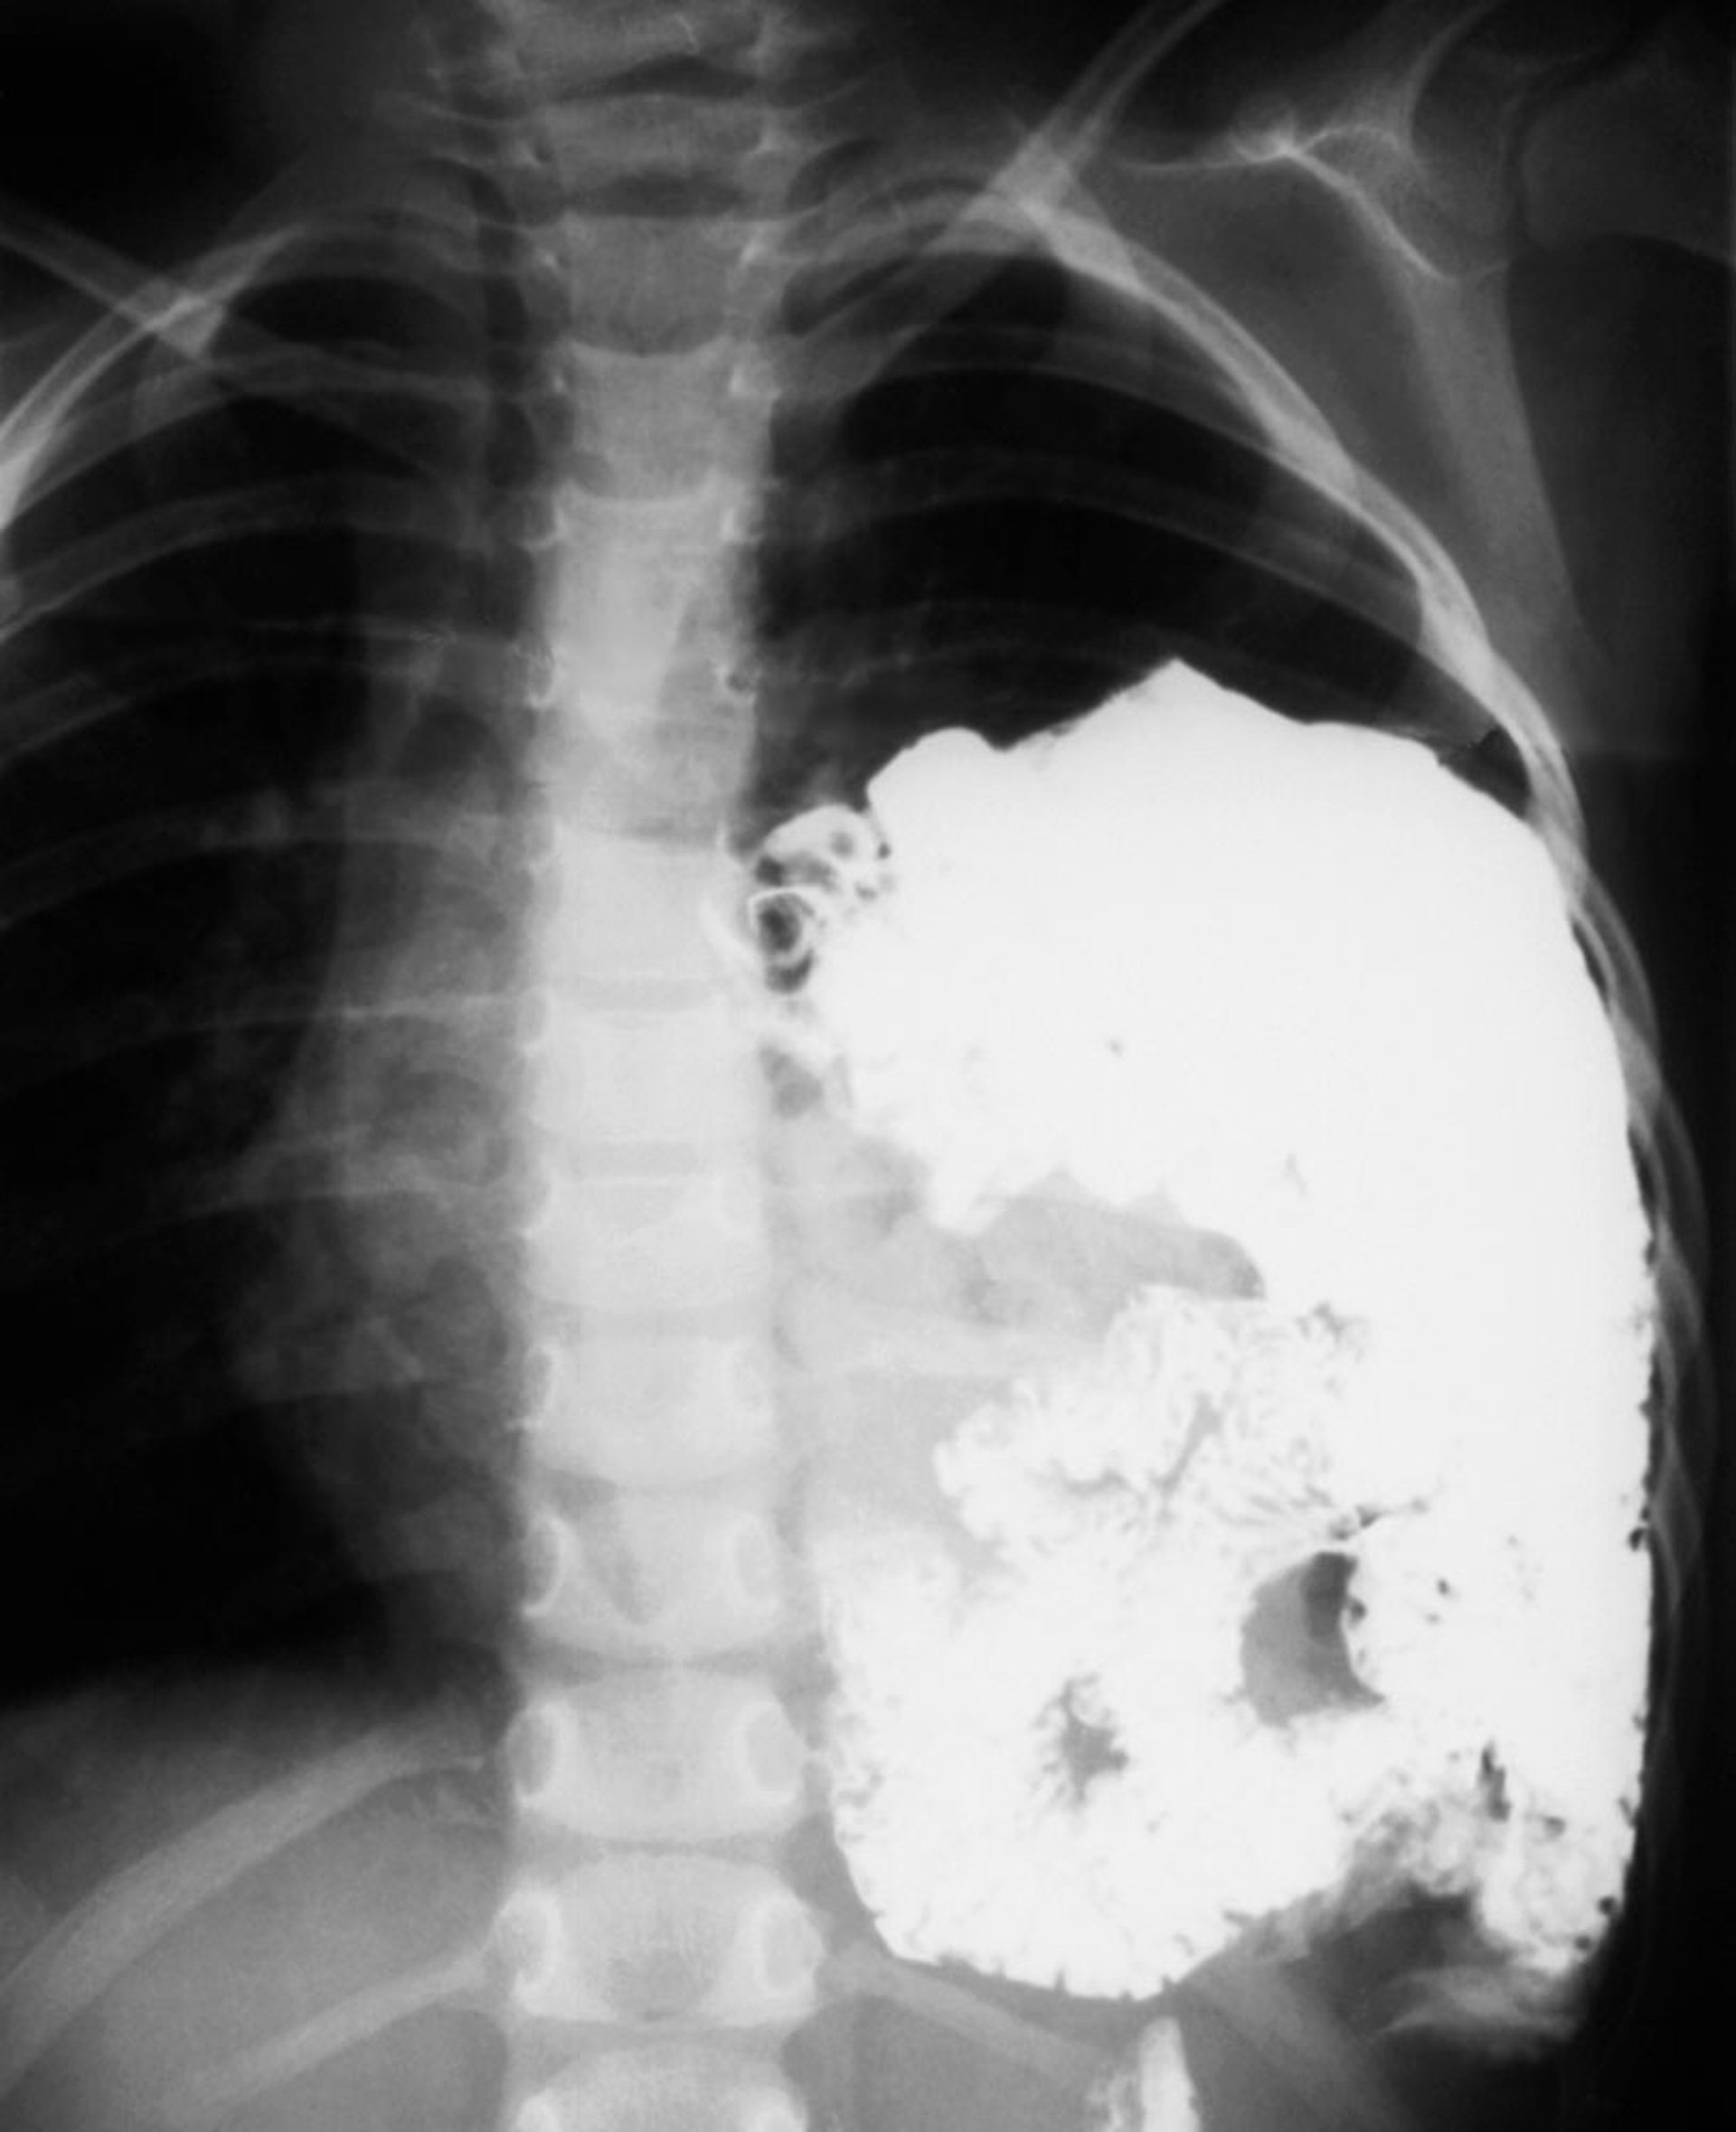

Después del parto, el diagnóstico es por radiografía de tórax, que muestra el estómago y el intestino desplazados hacia el tórax. En un defecto grande, se observan numerosas asas intestinales llenas de aire que ocupan el hemitórax y desplazamiento contralateral del corazón y las estructuras mediastínicas. Si la radiografía se efectúa inmediatamente después del parto, antes de que el recién nacido haya tragado aire, el contenido abdominal se visualiza como una masa opaca y sin aire en el hemitórax.

Hernia diafragmática

Esta radiografía muestra una hernia diafragmática congénita en un recién nacido. Los intestinos (asas blancas) sobresalen en el lado izquierdo del tórax (lado derecho de la radiografìa).

DU CANE MEDICAL IMAGING LTD/SCIENCE PHOTO LIBRARY